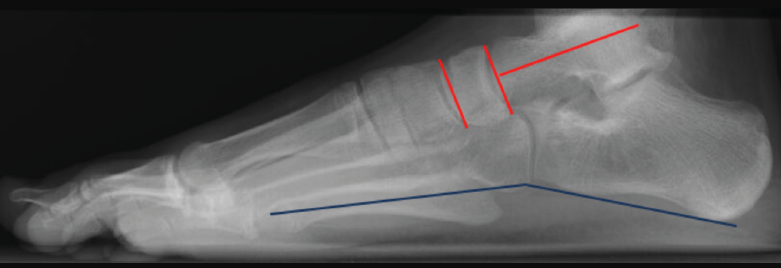

Para determinar el patrón anatómico del pie plano(3), se valora en la radiografía lateral en carga dónde está el vértice de la deformidad mediante los siguientes ángulos (Figura 7):

Figura 7. Radiografía lateral en carga de un pie normal. Ángulos utilizados para determinar el patrón anatómico del pie (rojo). El ángulo entre los puntos inferiores del calcáneo y el quinto metatarsiano (azul), si está disminuido, nos orienta para el diagnóstico de pie plano cavo.

• Ángulo entre el eje longitudinal del astrágalo y la superficie articular navicular (normal: 90°).

• Ángulo entre las superficies articulares del navicular y la superficie articular distal del primer cuneiforme (N1C) (normal: 0°).

• Ángulo entre los puntos inferiores del calcáneo y el 5° metatarsiano (normal: 160°).